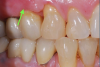

Individual anterior custom abutments should have straight or concave transmucosal profiles extending to the desired gingival line at the FMG (Figure 29 through Figure 35).

(29.) Single anterior custom abutment workflow.

Figure 29

(30.) Single anterior custom abutment workflow.

Figure 30